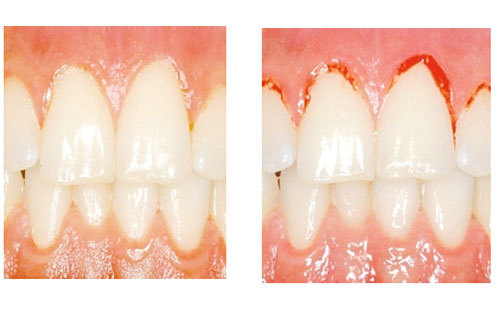

Ett inflammerat tandkött kan se helt friskt ut. Petar man på ett inflammerat tandkött så blöder det.

Inflammerat tandkött

En inflammation i tandköttet kan vara början till parodontit. Och det är placket som bildas i munnen som är orsaken till tandköttsinflammation (gingivit). Inflammation utan parodontit är enkel att behandla. Med förbättrad munhygien läker det oftast ut på en eller ett par veckor. Dock kan inflammationen komma tillbaka snabbt om munhygienen försämras. Noggrann rengöring med tandborste, tandtråd eller liknande är det enklaste knepet för att undvika inflammerat tandkött.